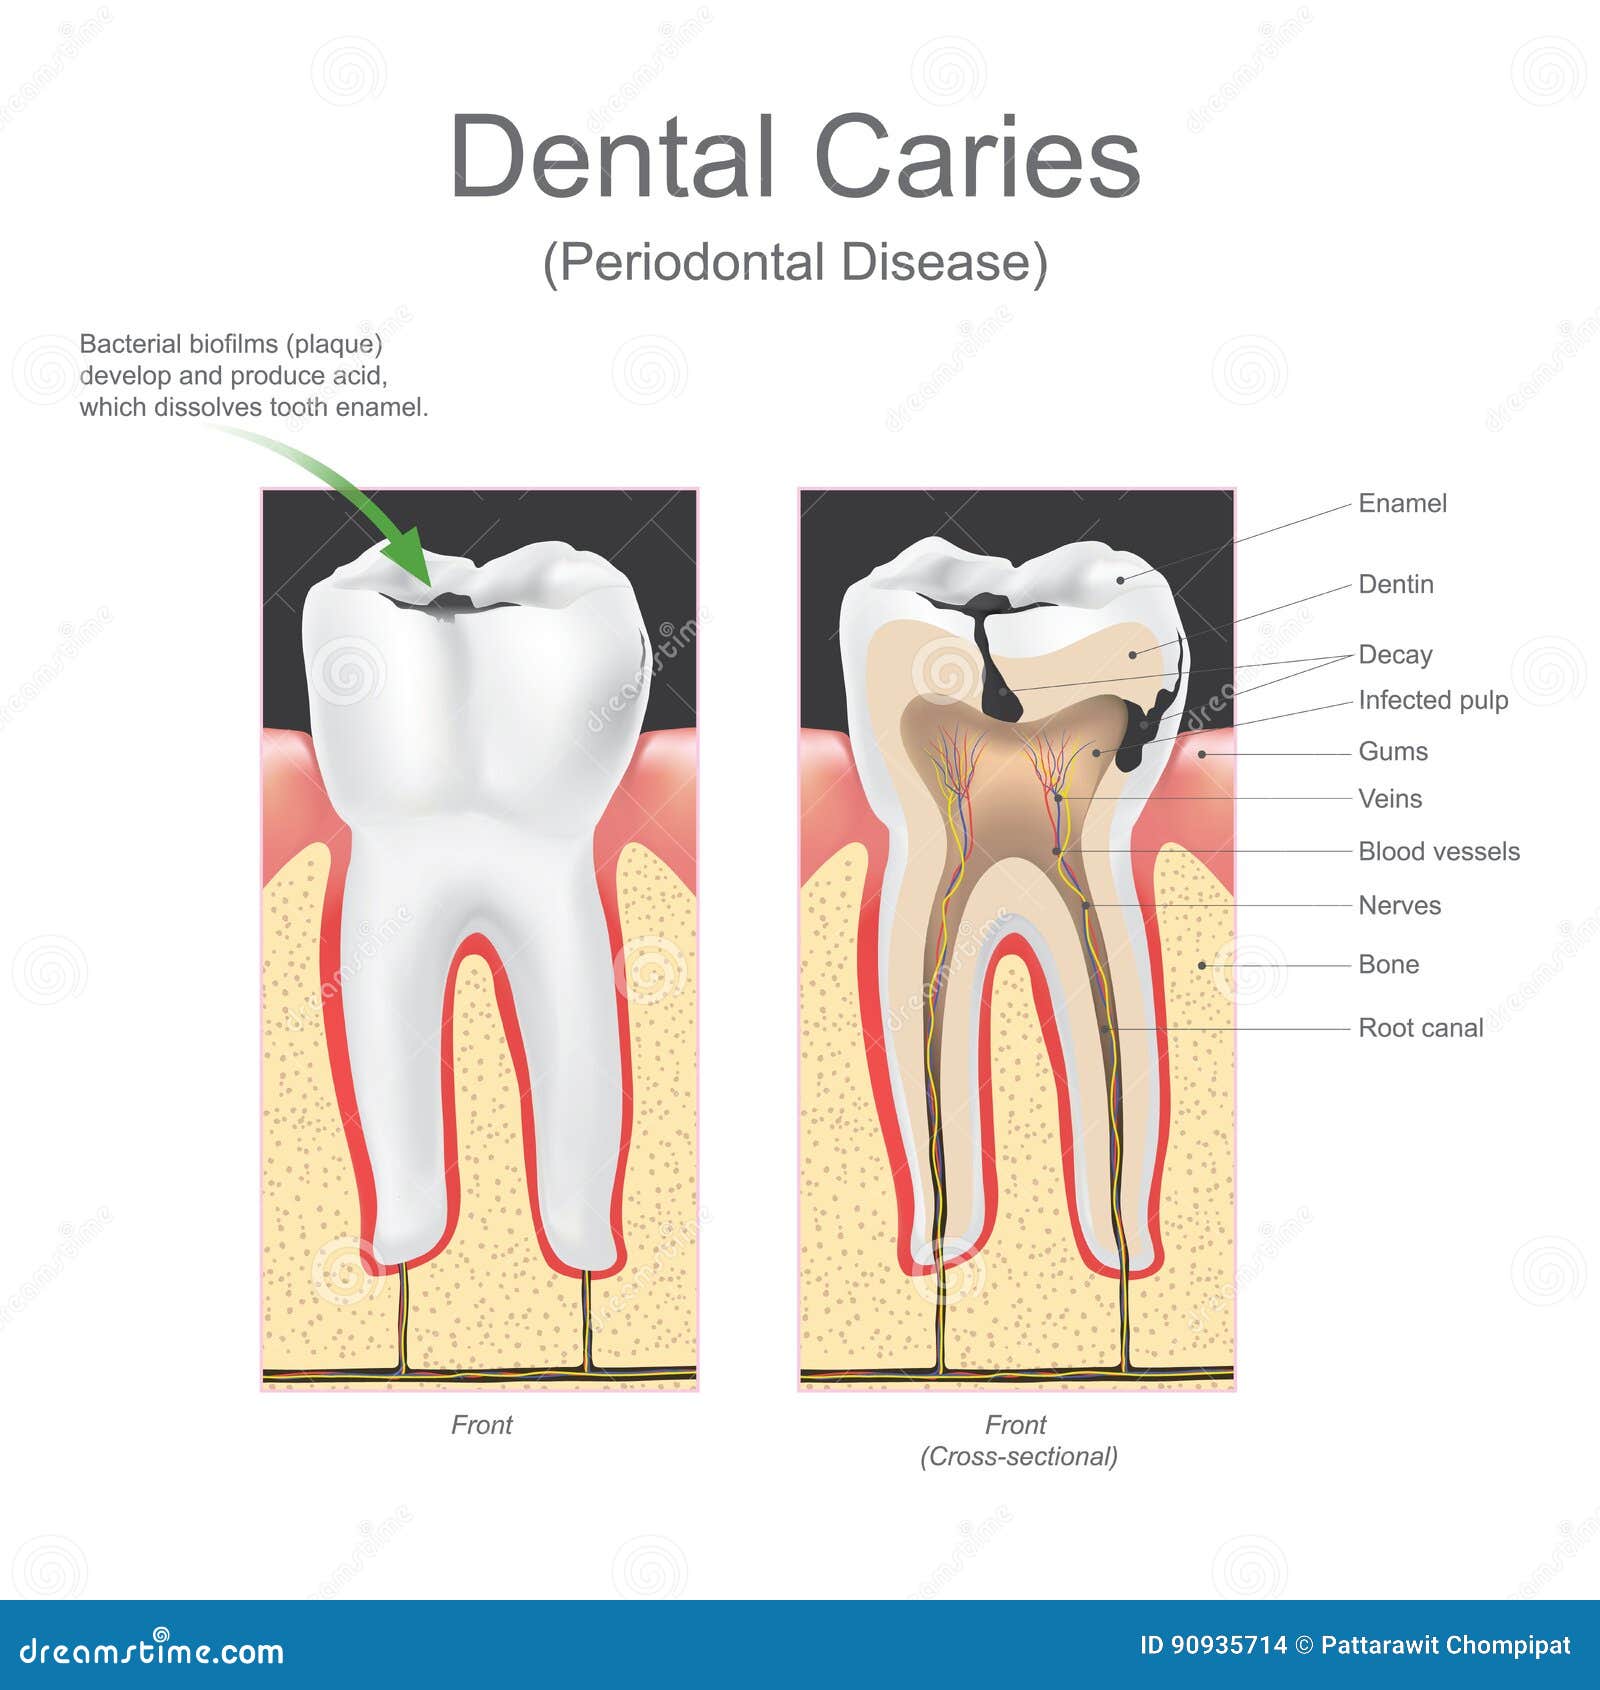

caries dental periodontal disease bacteria caused types tooth

Tooth dental decay abscess stages caries dentagama phoenix pain pulp infection teeth bone like spread look mouth periodontal severe enamel. Symptoms and treatments of dental caries. Stages of dental decay and periodontal disease